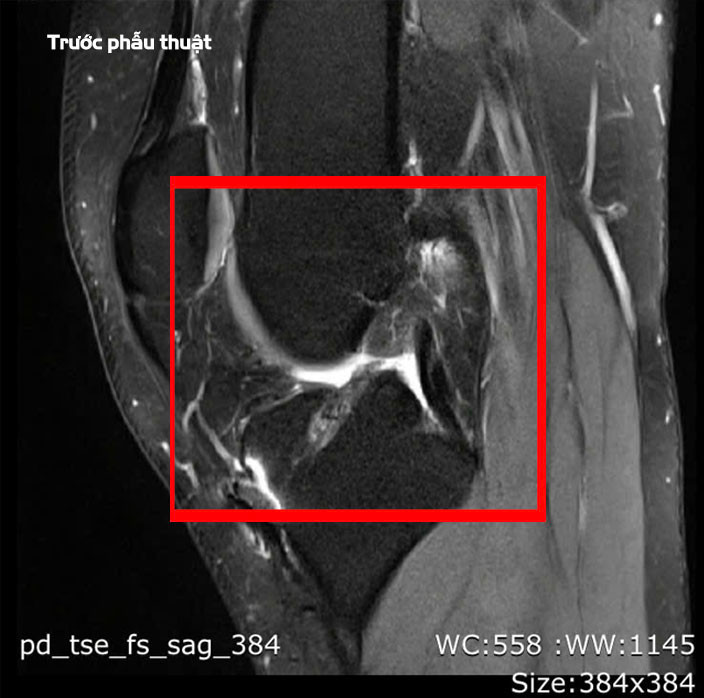

BSCKII Lê Hoàng Văn Hải, Trưởng khoa Chấn thương Chỉnh hình cho biết, qua thăm khám lâm sàng và chụp MRI, chúng tôi xác định bệnh nhân bị đứt hoàn toàn dây chằng chéo trước. Với trường hợp phẫu thuật lần thứ ba này, ê-kíp đã lựa chọn phương pháp tái tạo bằng gân hamstring kết hợp kỹ thuật All-Inside để tăng kích thước mảnh ghép.

Ca phẫu thuật được thực hiện vào ngày 18/2, kéo dài 90 phút và diễn ra thuận lợi. Ê-kíp phẫu thuật đã xử lý triệt để phần dây chằng cũ và đường hầm xương cũ, đồng thời tái tạo mới nhằm tối ưu hóa khả năng liền gân và xương.

![]() |

| Tổn thương dây chằng trên phim chụp - Ảnh BVCC |